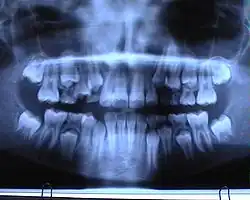

Jest to zdjęcie przeglądowe przedstawiające ogólny stan wszystkich zębów, zawiązków zębów oraz struktur je otaczających takich jak kości szczęki i żuchwy, stawy skroniowo-żuchwowe i częściowo zatoki szczękowe, jest również pomocne w ocenie wad rozwojowych[1], urazach i nowotworach.

Za pomocą pantomogramu można wykryć wiele nieprawidłowości, jak np. próchnica, zmiany okołowierzchołkowe, zęby zatrzymane, dodatkowe i nadliczbowe, zęby nieprawidłowo przeleczone kanałowo. Ze względu jednak na ogólny obraz czasami wymagane jest wykonanie dodatkowo dokładniejszego zdjęcia zębowego podejrzanej okolicy. Pantomogram daje również pogląd na stan kośćca w przypadku planowania zabiegu wszczepiania implantów zębowych – jednak w tym wypadku najczęściej korzysta się z tomografii komputerowej.